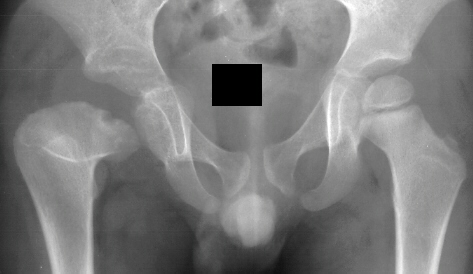

This case is an example of untreated septic arthritis which caused avascular

necrosis of the proximal femur. The primary cause of this is undrained

septic hip. Repeated aspiration is not adequect treatment of a septic hip.